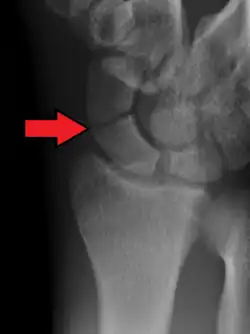

Le diagnostic de fracture est difficile à réaliser car les lésions éventuelles peuvent ne pas être immédiatement visibles sur les radiographies standard du poignet de face et de profil. On pratique aussi une radiographie avec incidences spéciales (inclinaison de 30° vers le coude) qui permettent de dérouler l'os et ainsi de visualiser plus précisément le trait de fracture[5].

Dans 1/4 des cas, l'examen clinique fait penser à une fracture, mais la radio ne le montre pas, alors qu'il y a réellement une fracture[6].